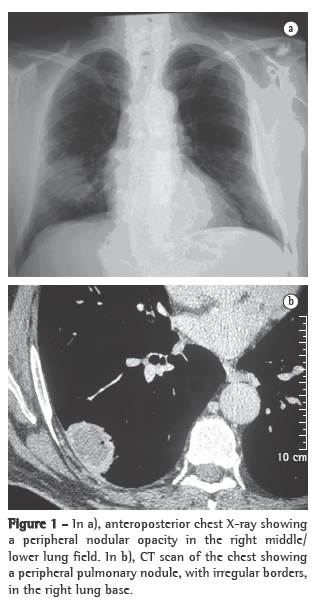

Case reportA 61-year-old male patient sought treatment at the pulmonology outpatient clinic reporting lung secretion with occasional bloody sputum for approximately 5 months. Within the past month, the patient had severe cough, dyspnea and a peak of fever. The patient reported no other respiratory problems and no history of occupational risk. He also reported long-term labyrinthitis and recent hypoacusis. He was a former smoker (30 pack-years) who had not smoked for 10 years. The physical examination revealed that the patient was well hydrated and with good color. He presented abnormal breath sounds, crackles in the right hemithorax base, increased vocal fremitus and a systemic arterial pressure of 120/80 mmHg. The SpO2 was 96%. The investigation began with imaging studies and laboratory tests. A chest X-ray showed a nodular opacity in the lower third of the right hemithorax (Figure 1a), a sinus X-ray revealed thickening of the left maxillary sinus mucosa, and a CT scan of the chest revealed an extensive lesion in the right hemithorax (4.2 cm × 3.1 cm), contiguous with the parietal pleura (Figure 1b). Based on these findings, we requested a tomography-guided percutaneous biopsy, which showed areas of fibrosis and areas of extensive necrosis associated with an inflammatory process (Figures 2a and 2b), whose possible causes include WG, bronchocentric granulomatosis or an infectious disease.

Imaging studies showed an extensive unilateral nodular lesion. This finding is uncommon in WG and, therefore, there was diagnostic difficulty in view of the possibility of a malignant disease. What is expected in this type of vasculitis is pulmonary infiltration or bilateral multiple nodules, which can be accompanied by cavitations (in 50% of the cases).(8) The next step was then to resort to tomography-guided percutaneous biopsy, a procedure that has high sensitivity, specificity and accuracy, the last ranging from 84.5% to 90%, depending directly on the size of the lesion. The principal reason for requesting the procedure is to determine malignancy in solid pulmonary lesions.(9,10)